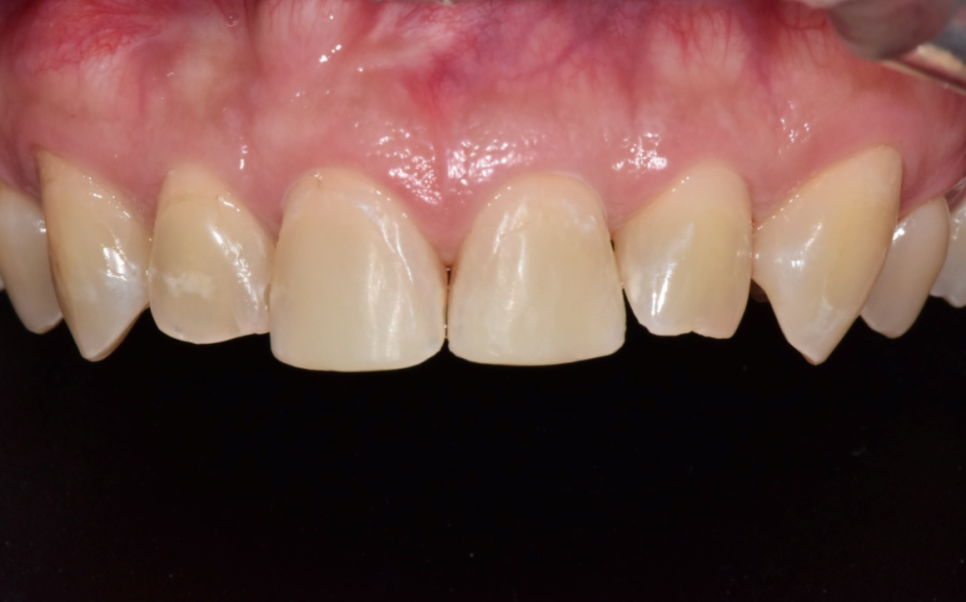

그래서 내원한 당일에 레진으로

자연스럽게 앞니 형태를 회복해 드렸습니다.

환자분도 깨지기 전 모습 그대로 돌아온

앞니를 보시며 안도하시는 표정이셨습니다.

이 환자분은 1세대 실손보험을 가지고 계셨고,

치아파절 실비 청구가 가능한 상황이었죠.

그래서 필요한 서류를 제출하실 수 있도록 안내드렸습니다.

결과적으로 비급여인 앞니 레진 치료 비용까지

보상을 받으실 수 있었습니다.